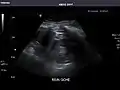

Right kidney

Kidneys: Right and left kidneys measure 11.5 cm and 12 cm in length respectively. No hydronephrosis. Small left lower pole kidney cyst.